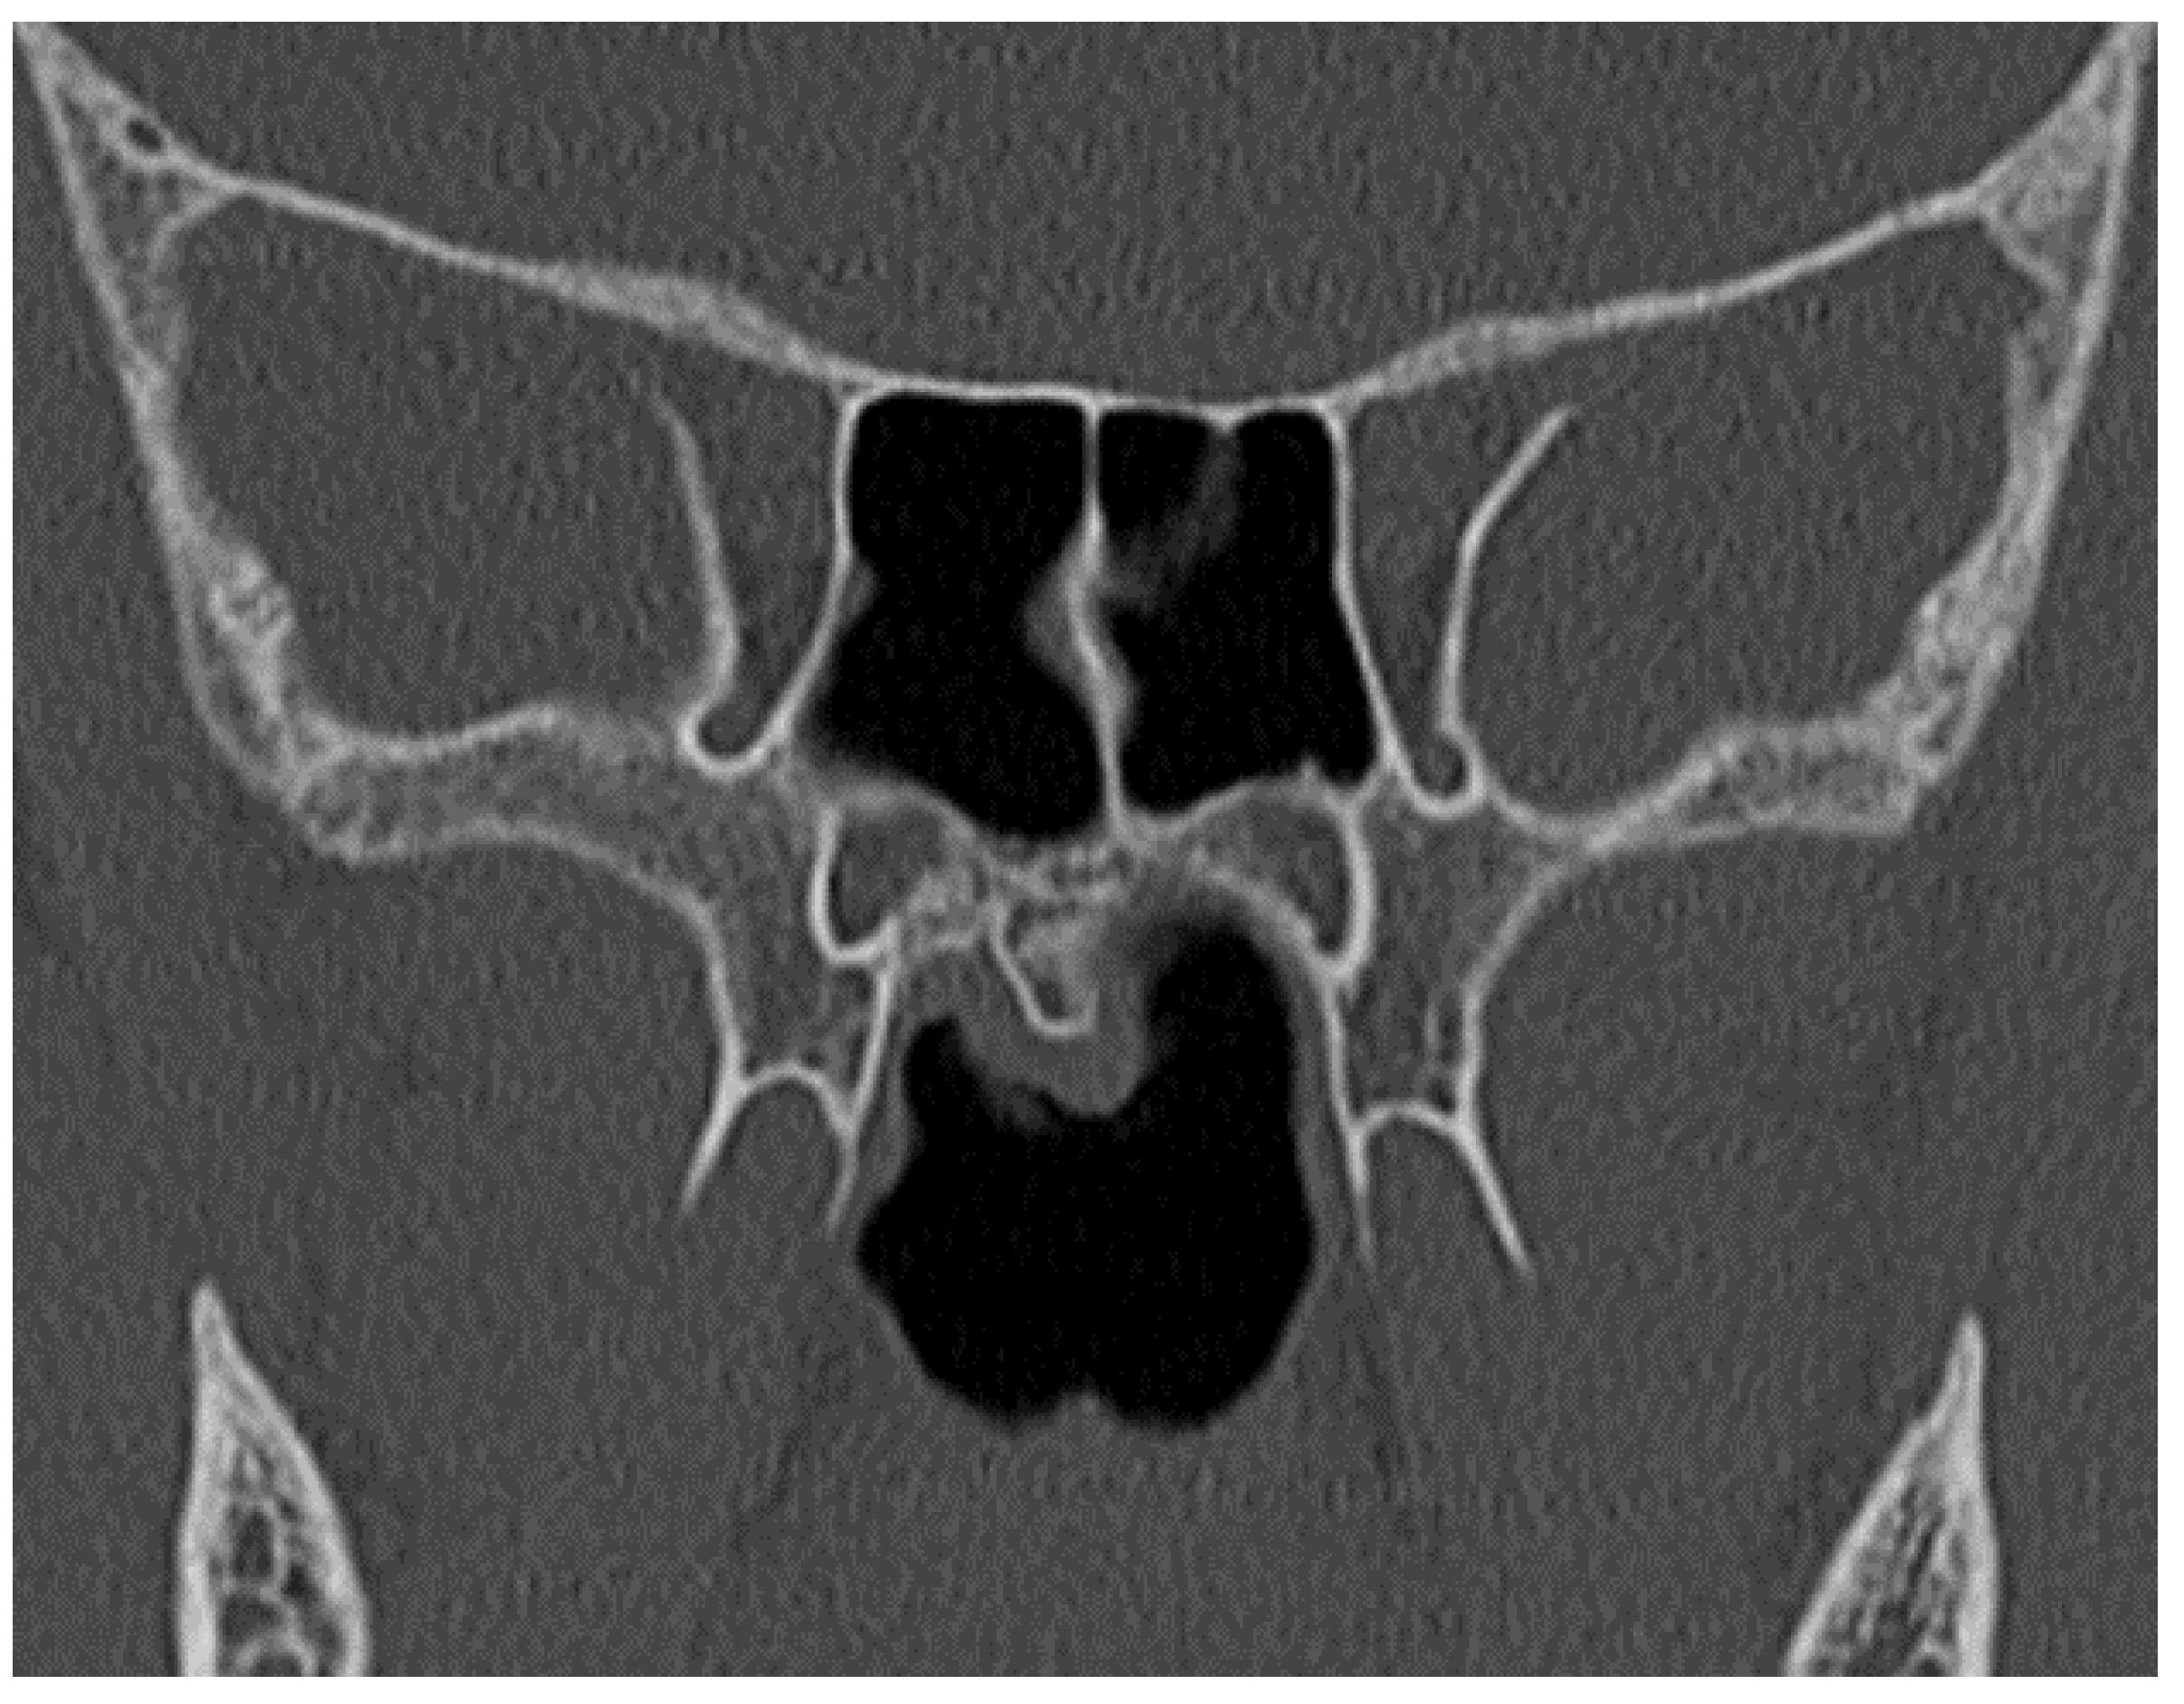

| Anterior bone width (ABW) | The distance between the two ridges protruding from the anterior wall of the maxillary bones |

| Bone width of choana (BCAW) | The distance between the two pterygoid processes |

| Posterior right bone width (RPBW) | The distance between the lateral bone wall of the right nasal cavity and the mucosa of the septum |

| Posterior left bone width (LPBW) | The distance between the lateral bone wall of the left nasal cavity and the mucosa of the septum |